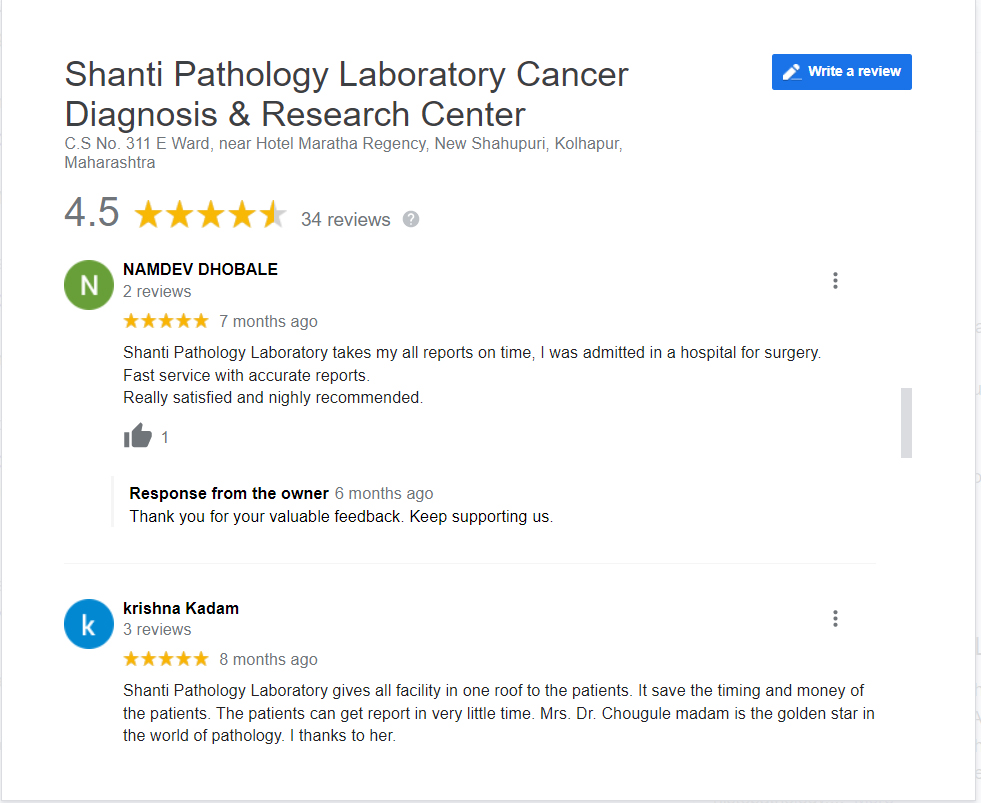

Dr. Meghana Chougule is the chief consultant pathologist at Shanti Pathology Laboratory Cancer Diagnosis & Research Center, Maharashtra.